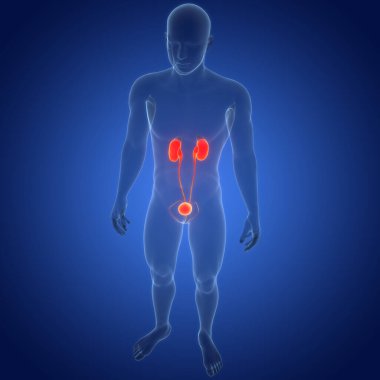

İnsan vücudundaki böbreklerin hologramı. Geleceğin sağlık hizmetleri. Modern tıp bilimi. 3B illüstrasyon, 3B canlandırma

ArkaplanresimlemeİnsanSağlıksağlıklıİlaçSağlık hizmetleriHastalıkTıbbidikkatteknolojiçizgi filmGeleceğe yönelikDoktorHastaneAygıtDijitalgövdeterapiTedavibiyolojiBilimkanserSistemGözlüklerAcıYenilikorgKulaklıktaşlaranatomiklinikİşlemOrgan nakliBöbreklerBöbrekHologramçokgenÜroloji3d oluşturma3B illüstrasyonpiyelonefritBenzer İçerikler